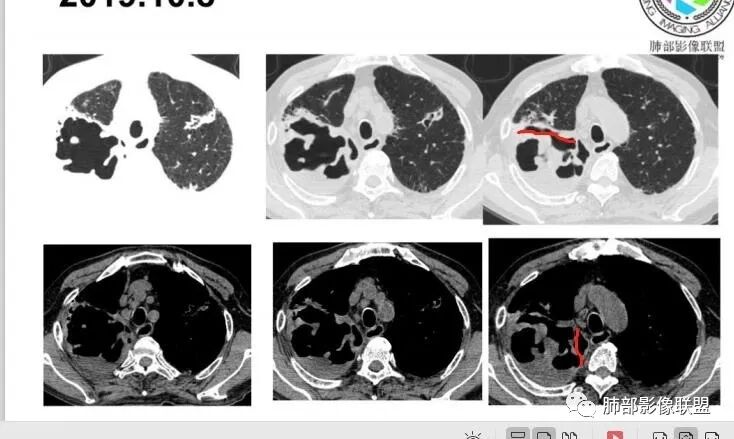

2.双肺多发病灶,主要集中在右肺,斑片影、结节影,条索影,支扩等等,右肺病灶胸膜下居多,密度偏高不均,偶见钙化。

3.右肺巨大空洞影。值得注意的是:

1)空洞内坏死相对彻底(未见絮状物或丝状物等)。

2)空洞壁密实,内外壁都清楚,这是慢性病灶特征之一。

3)内壁不规则,多呈不规则山脊样突入,这些“脊”等同于空洞壁的密实。尽管洞腔内蜿蜒不规则,但并未形成洞壁的膨隆样结节影,换句话说,外壁看不出分叶!

这种空洞更多见于结核!

4)空洞病灶内显示液平。提示伴有细菌感染等。

5)肺门纵隔未见肿大淋巴结。